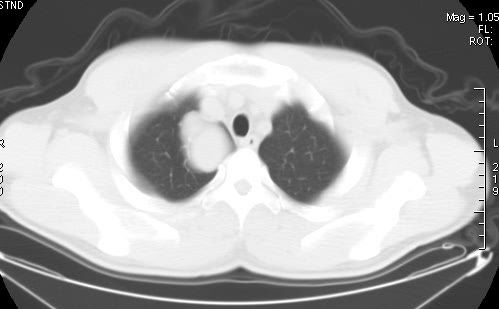

标题: CT7610:[原创]右上纵隔还是肺内占位,请会诊!

体检发现,无任何不适。

定性:考虑支气管囊肿可能性大。(增强强化不明显)

不过重建的图片上看到肿块内可见强化的血管影,不是很支持。

右肺见纵隔旁见类圆形界清等密度肿块影,直径约5.0cm,增强呈不均匀强化,重建的图片上看到肿块内可见强化的血管影,考虑:1,肺腺瘤;2,肺肉瘤。